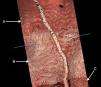

We report an example of successful treatment of a coronary intervention complication with three different kinds of stent. Currently BVS are much less navigable than metal DES; this case is a good example on this characteristic. OCT images show the interface between the resorbable scaffold, the polymer layer of the stent graft and the metal strut of the distal DES (Figures 1 and 2). Figure 3 shows the stent graft overlapping the BVS.